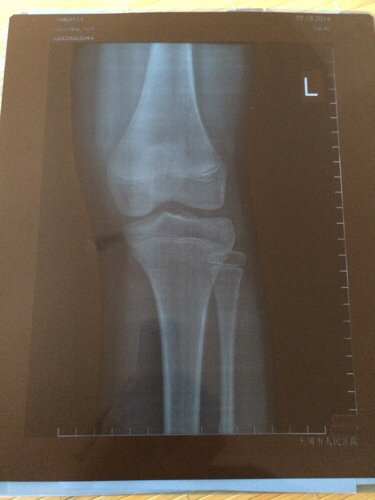

你好!我女儿十周岁半,13号就来了月经,可她的身高只有140,体重60斤,我现在想知道发育后身高还有可能长多少厘米,这些片子是我今天在医院拍的,可我看不懂 ,是什么意思,看片子孩子骨头还有可能长高吗?希望医生帮帮我,需要你们回答清楚点。非常感谢